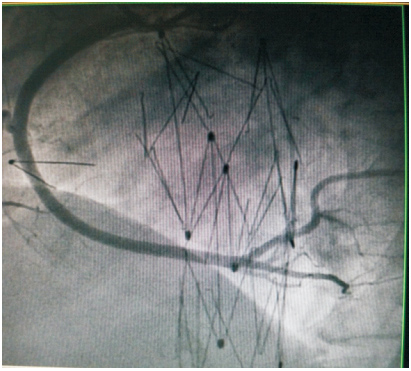

患者59岁,女性,因“发现心脏杂音3个月”于2011年1月份入院。患者2001年因下腔静脉狭窄于外院行下腔静脉支架植入术(支架厂家及型号不详),术后服用培达3个月后停药,无不适。2007年间断出现心悸及胸闷,未诊治。2011年单位体检发现心脏杂音,外院超声提示下腔静脉支架移位至右房,主动脉窦右房瘘。既往:体键。入院查体:血压120/70 mmHg(1 mmHg=0.133 kPa),心律齐,主动脉瓣第一听诊区可闻及Ⅲ/6级收缩期杂音,腹软,无压痛,双下肢不肿。入院诊断:下腔静脉狭窄,下腔静脉支架植入术后,下腔静脉支架移位,主动脉窦右房瘘。入院后相关检查:超声心动图:LV 53 mm,EF 74%,主动脉右冠窦与右房间探及破口约3~4 mm,下腔静脉入右房口处探及支架回声,支架突入右房约20 mm;胸片(图 1、2):侧位片金属支架结构影不连续,心影区偏前区可见线状高密度影。CT(图 3、4):右室游离壁、间隔壁、三尖瓣口、右房、下腔静脉近心段可见支架金属丝影。冠状动脉造影检查(图 5、6):冠状动脉未见明显异常,可见支架影随着心脏的跳动位置发生变化。